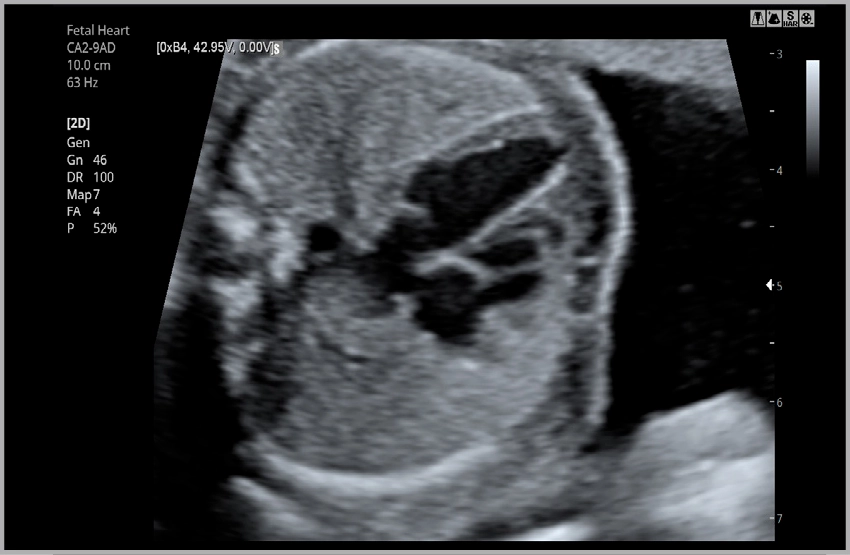

Сердце плода